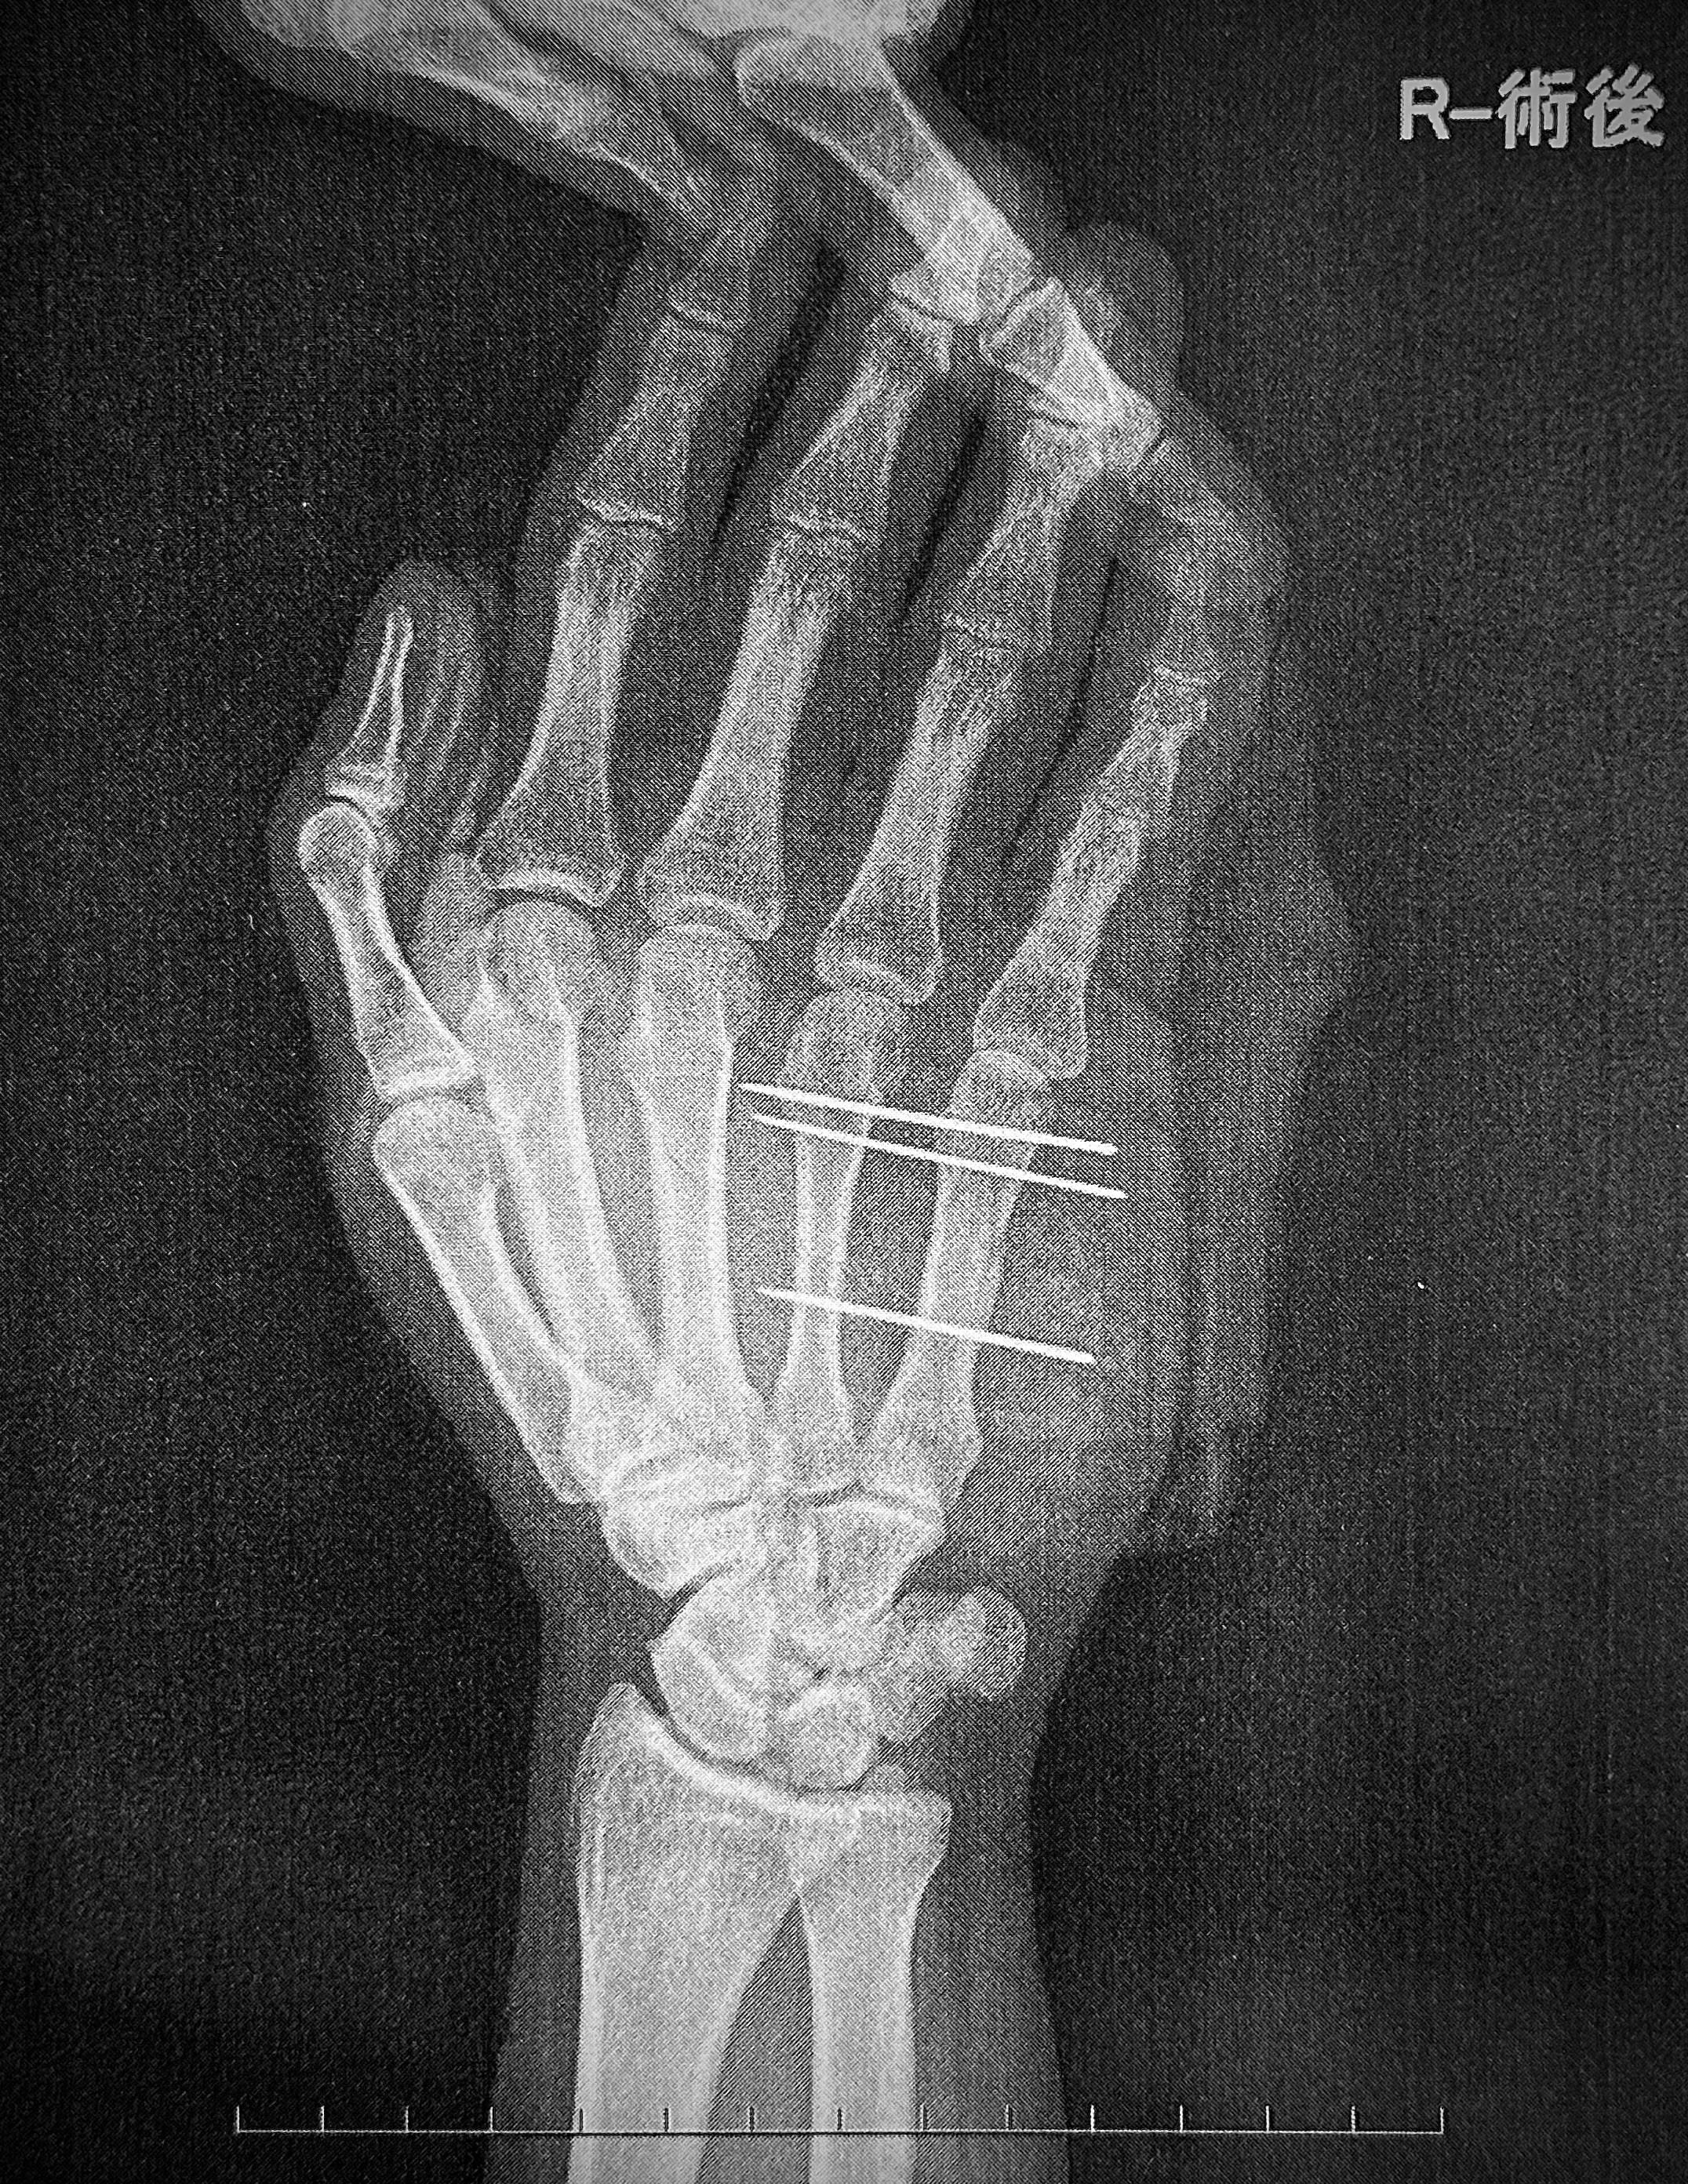

最近、私自身が強盗未遂に遭い、犯人を取り押さえた際に骨折等、多々怪我を負い手術しました。

画像は自宅の防犯カメラの実際の写真とその際に犯人が使用した凶器です。

先日、私自身が強盗未遂に遭い、犯人と遭遇して取り押さえる際に利き手の骨折等多数の怪我をし手術しました。